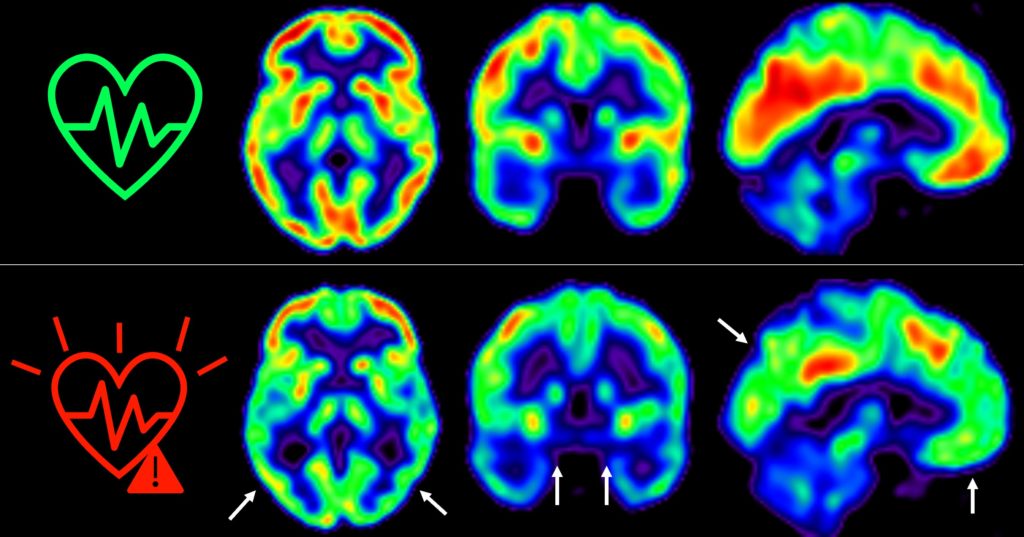

En 2021, los investigadores del CNIC descubrieron que la presencia de factores de riesgo cardiovascular y de aterosclerosis subclínica -antes de que aparezcan los síntomas- en las arterias carótidas, que son las que suministran sangre al cerebro, en individuos de 50 años aparentemente sanos que participan en el estudio PESA-CNIC-Santander, estaba asociada a un menor metabolismo de glucosa cerebral (Cortés-Canteli & Gispert et al. JACC. 2021). El metabolismo de la glucosa cerebral está considerado un indicador de salud cerebral.

El equipo del Dr. Valentín Fuster, liderado por los Drs. Marta Cortés Canteli y Juan Domingo Gispert, han seguido a estos individuos a lo largo de 5 años y han encontrado que aquellos que mantienen un riesgo cardiovascular elevado durante todo este tiempo sufren una disminución aún mayor del metabolismo cerebral medido a través de técnicas de imagen como tomografía por emisión de positrones (PET).

“Hemos detectado un declive metabólico cerebral tres veces mayor que el de personas que se mantienen en bajo riesgo cardiovascular”, señala Catarina Tristão-Pereira, primera firmante del artículo y becaria INPhINIT de la Fundación ”la Caixa”. La glucosa es la principal fuente de energía de las neuronas y otras células cerebrales. “Si el consumo de glucosa cerebral disminuye durante varios años puede limitar la capacidad del cerebro de lidiar en un futuro con enfermedades neurodegenerativas o cerebrovasculares”, asegura el Dr. Gispert, experto en Neuroimagen del CNIC y del Barcelonaβeta Research Center.

Además, el equipo del CNIC descubrió que la progresión de la aterosclerosis subclínica en las carótidas durante estos 5 años se relacionaba con una disminución del metabolismo en regiones cerebrales vulnerables a la enfermedad de Alzheimer, de manera aditiva al efecto de los propios factores de riesgo cardiovascular. “Estos resultados corroboran que la detección por imagen de la aterosclerosis subclínica aporta información muy relevante”, añade el Dr. Fuster, investigador Principal del estudio PESA. “La relación entre el cerebro y el corazón es un tema fascinante y con este estudio hemos visto que empieza mucho antes de lo que se creía”, continúa.